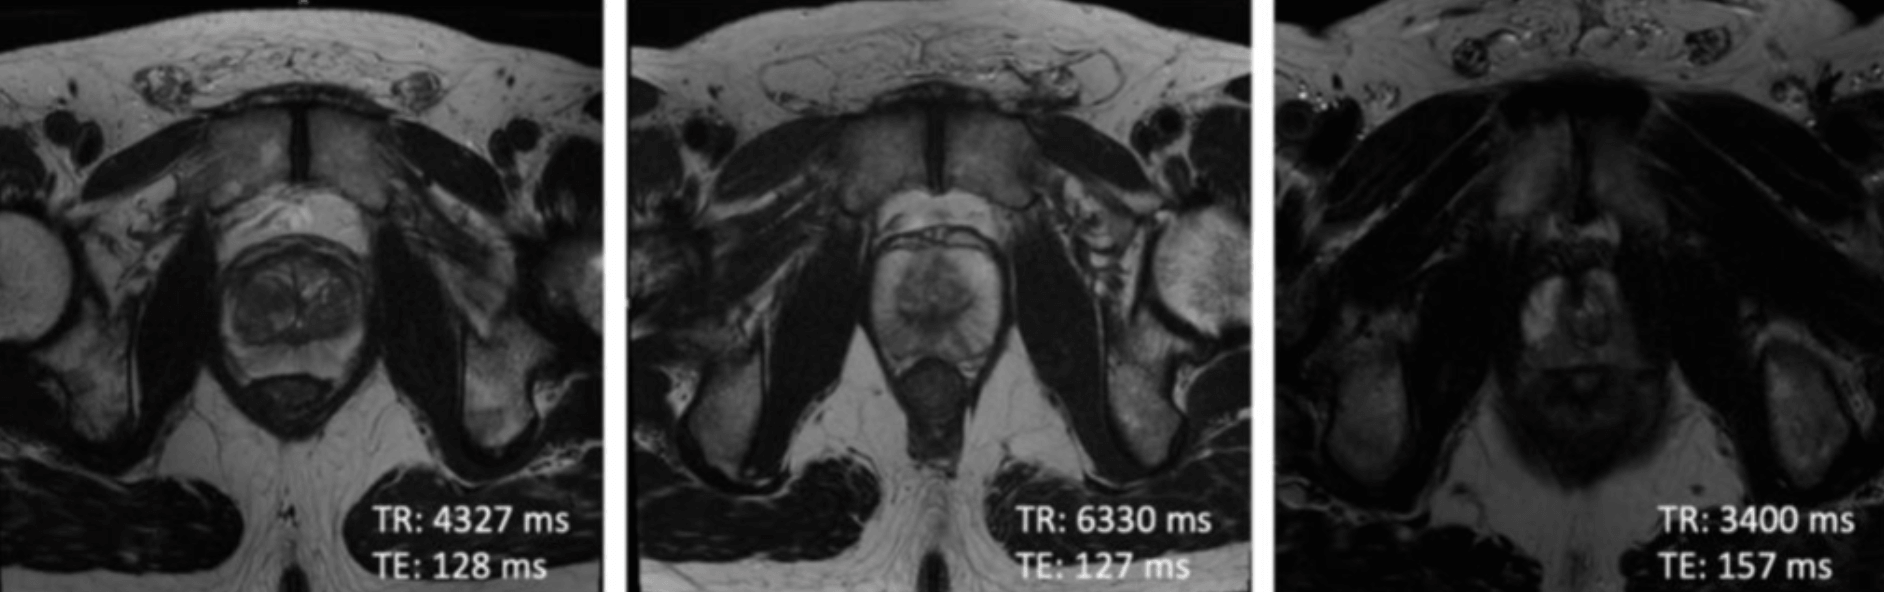

We regularly see image variations in data analysis, particularly when handling real-world data from multiple imaging centers. These discrepancies can stem from different scanner manufacturers, scanner models or acquisition protocols. This leads to notable differences in image intensity values. Such variations present substantial challenges in creating universally applicable and reliable models1. They also impact the reproducibility of quantitative imaging biomarkers and radiomics features2, crucial for developing clinical decision support systems. This variability is particularly prominent in Magnetic Resonance (MR) images because, unlike Computed Tomography (CT) scans, where intensity values are standardized to Hounsfield Units (which also require certain degree of harmonization), MR image intensities are not normalized to a standard unit of measurement. As can be observed in Figure 1, MRI scans acquired with different echo times (TE) and repetition times (TR) result in differences in image intensities.